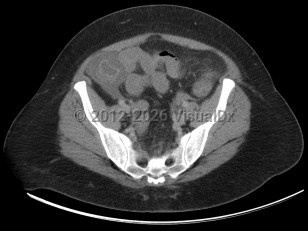

Neutropenic enterocolitis

Neutropenic enterocolitis commonly presents with right lower quadrant abdominal pain, diarrhea, and fever with underlying neutropenia or immune compromise. Patients can develop severe sepsis with end-organ damage and bowel perforation with progressive neutropenic enterocolitis. Early recognition and treatment of sepsis with intravenous antibiotics and volume resuscitation, along with surgical intervention if necessary, are the hallmarks of treatment that can improve mortality. If untreated, neutropenic enterocolitis can be fatal.